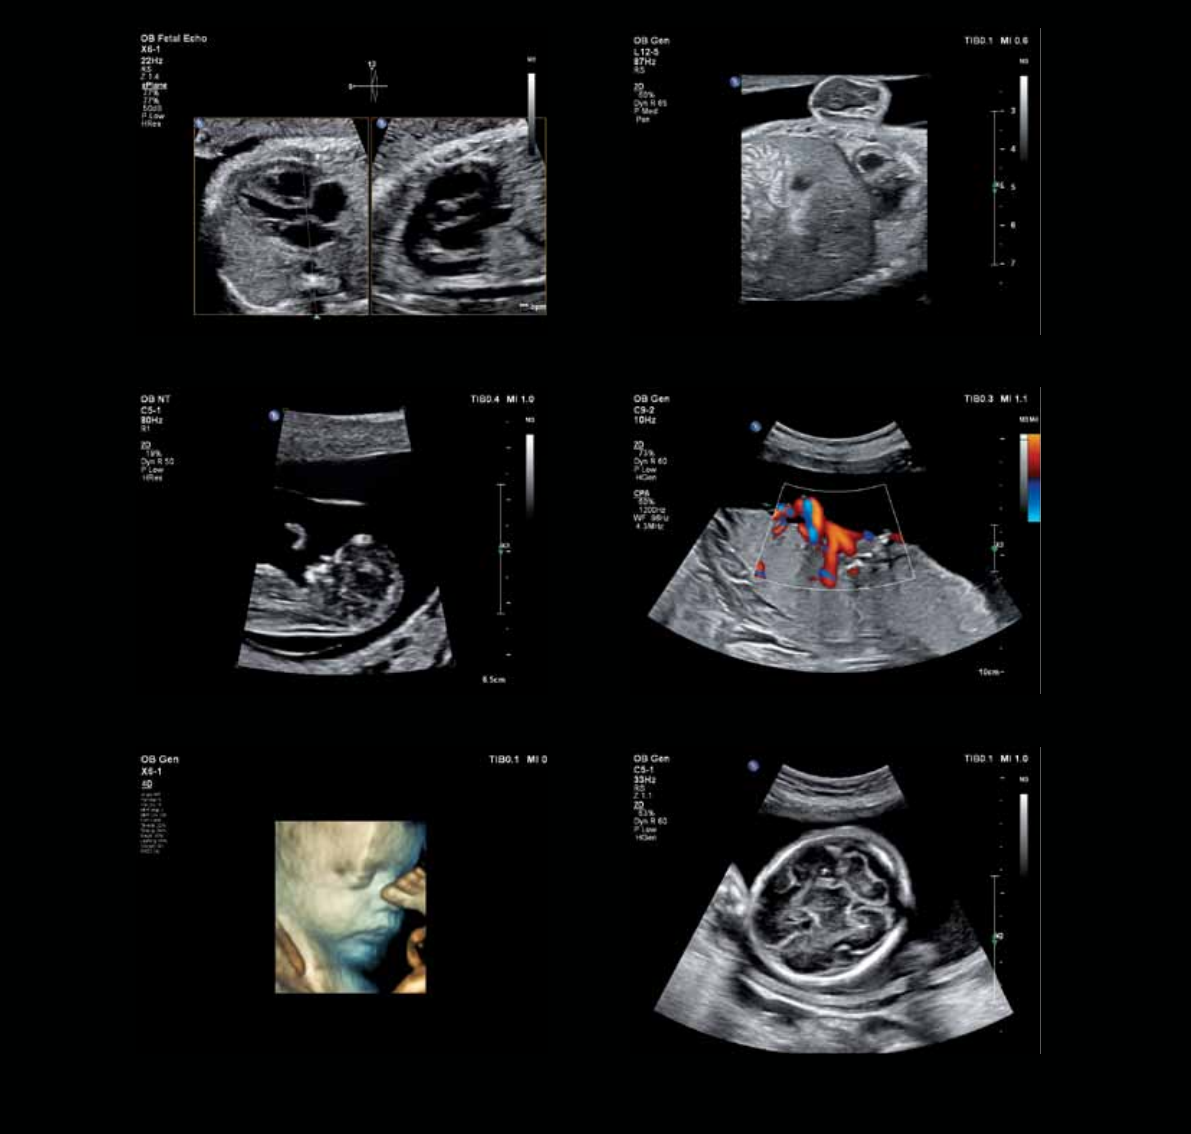

Fetal heart, Live xPlane Fetal diaphragm

Placental cord insertionNuchal translucency

CerebellumFetal face

Exceptional images

for a new era

13

Intrauterine device Fetal spine

13-week fetal kidneyOvarian cyst

34-week gestationFetal abdomen